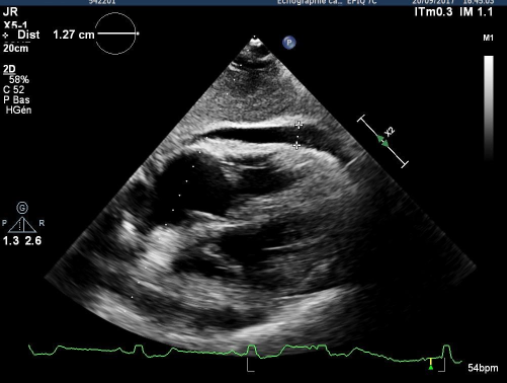

L'échographie est un excellent examen diagnostic pour l'IC.

5/ Cas clinique n°1 - Quel est votre lecture de l'ECG

Cas clinique n°1 - Quel est votre lecture de l'ECG

6/ Cas Clinique n°1 suite - Découverte d'un BBG de novo le traitement actuel est COSIMPREL 10mg/jour + Furosémide 40 mg/jour

Cas Clinique n°1 suite - Découverte d'un BBG de novo le traitement actuel est COSIMPREL 10mg/jour + Furosémide 40 mg/jour